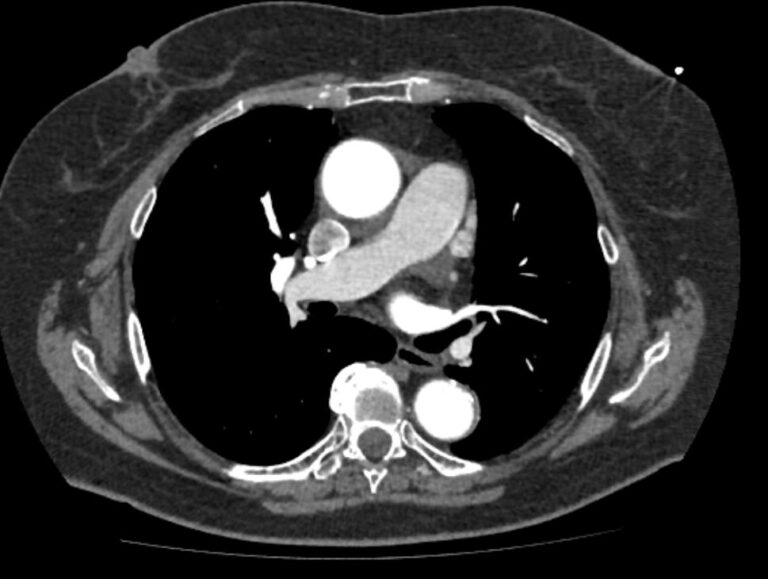

Грудная аорта делится на несколько отделов – восходящий отдел аорты, дуга аорты и нисходящий отдел. Корень аорты отходит непосредственно от левого желудочка, в его состав входят синусы Вальсальвы от которых берут начало коронарные артерии. После корня, прослеживается тубулярная часть восходящего отдела аорты, которая переходит в дугу аорты.

Дуга аорты дает начало брахиоцефальным артериям, которые питают головной мозг и верхние конечности. Затем следует нисходящий отдел аорты, распространяющийся через отверстие в диафрагме. От грудного отдела аорты отходят висцеральные артерии, кровоснабжающие органы средостения: бронхиальные, пищеводные, перикардиальные, медиастинальные артерии.

Одним из информативных методов диагностики сосудистой патологии является мультиспиральная компьютерная томография грудной аорты и ее ветвей (КТ-ангиография). Метод сканирования при помощи рентгеновских лучей и цифровой обработки данных позволяет получать послойные снимки сосудов и трехмерные реконструкции сосудистой системы в мельчайших подробностях.

Для того, чтобы качественно визуализировать сосудистую систему КТ-ангиография предусматривает в обязательном порядке применение контрастного усиления. Йодсодержащее контрастное вещество вводится пациенту внутривенно и, благодаря способности контраста поглощать рентгеновские лучи, ярко контрастирует сосудистую систему на фоне окружающих тканей.

КТ-ангиография позволяет диагностировать аневризмы аорты, сосудистые аномалии развития, воспалительные изменения стенок сосудов, пристеночные тромбы, сужения просвета сосудов за счет сдавления извне близлежащими опухолевыми образованиями.